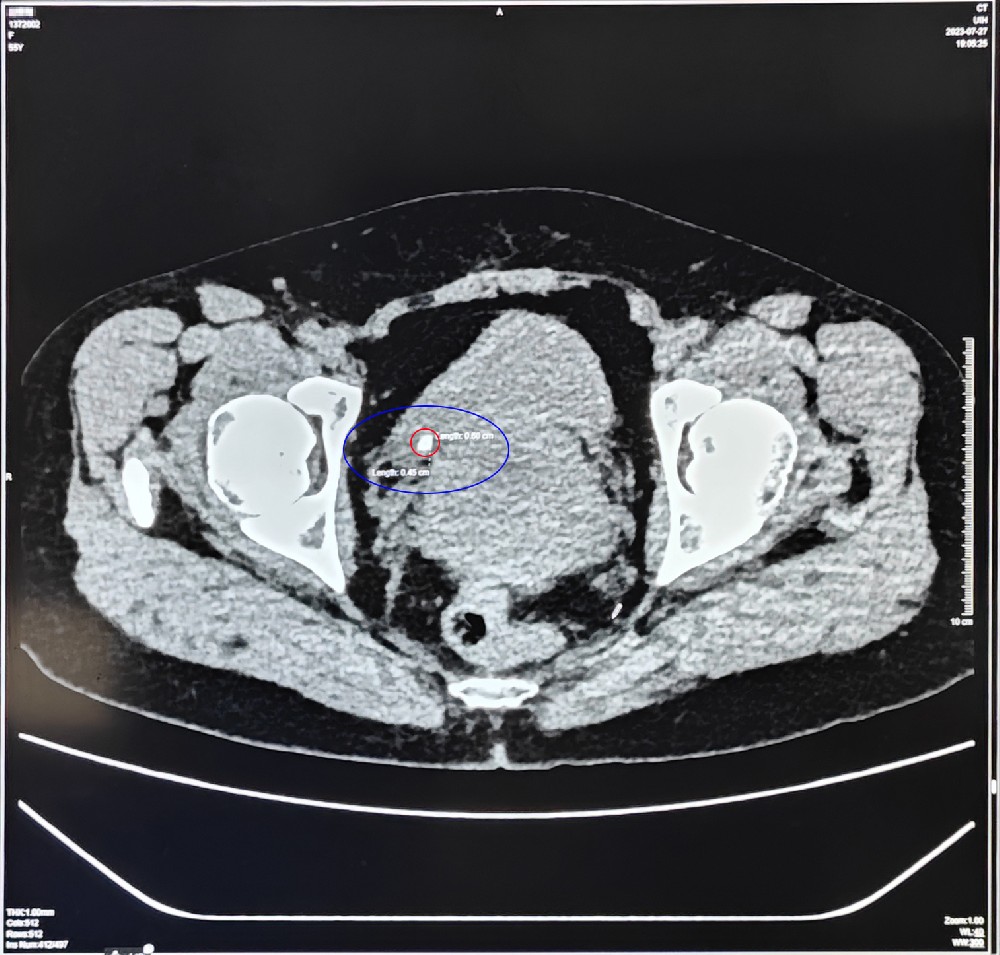

尿路有结石,疼的时候真要命……2023-08-01 83发布:院办